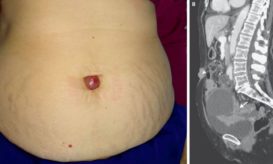

Ένα περίεργο εξόγκωμα ακριβώς στον αφαλό μια 73χρονης αποδείχθηκε ότι ήταν μεταστατικός καρκίνος, σύμφωνα με σχετική έκθεση που δημοσιεύθηκε...